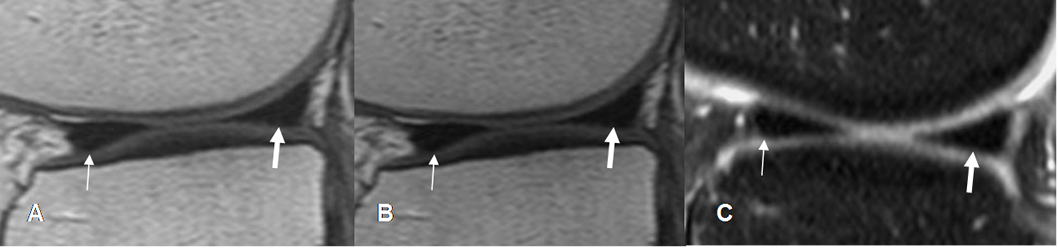

Fig 13. LCA normal.

A: RM sagital en T1, B: RM sagital en T2 y C: RM sagital en FFE. Ligamento normal,

hipointenso en todas las secuencias.

Fig 14. LCA normal.

RM coronal en T1. Bandas normales del LCA. Anteromedial (Flecha delgada) y posterolateral (Flecha gruesa).